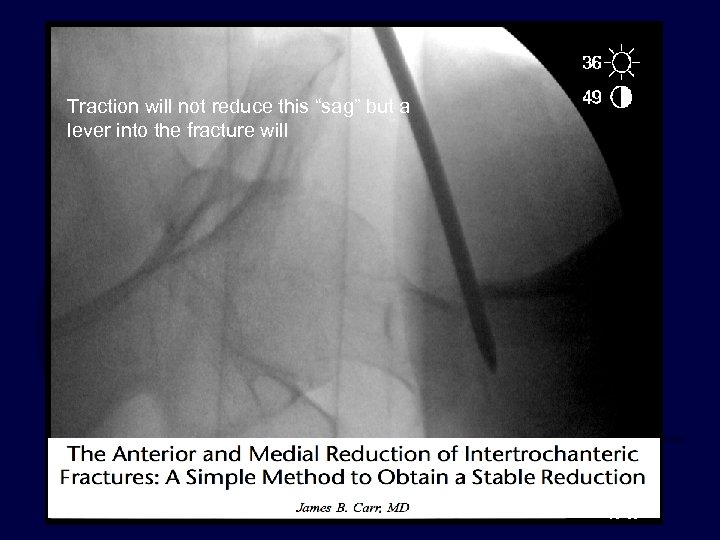

Surgeon controlled factor Fracture Reduction · Discuss sequence of closed reduction steps · Consider adjuncts to fracture reduction Crutch… elevator… joystick…. etc. Lever technique– read this article:

Traction will not reduce this “sag” but a lever into the fracture will

Traction will not reduce this “sag” but a lever into the fracture will reduce it

Surgeon controlled factor Fracture Reduction The AP view before and after lever redution: the medial cortex is restored